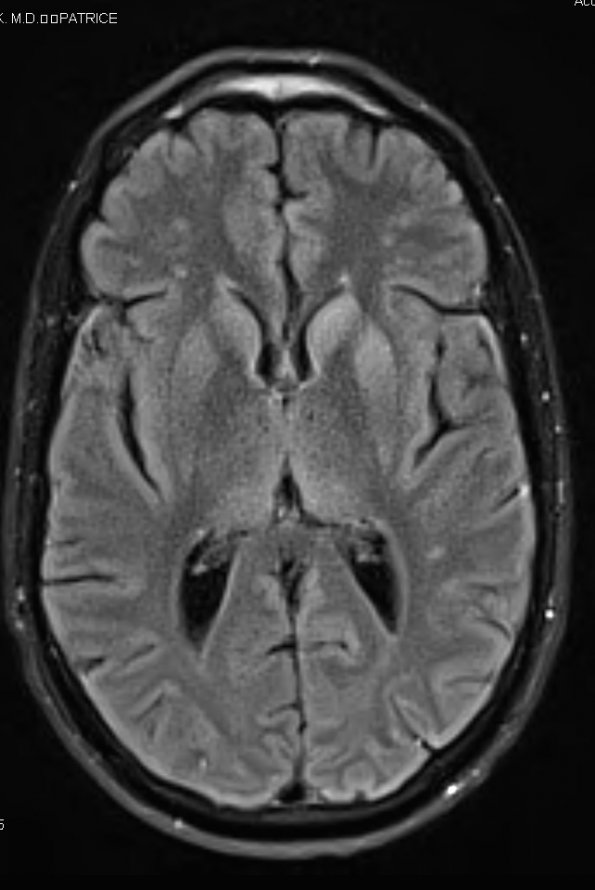

At autopsy the unfixed brain weight was 1140g. The cerebral hemispheres, cerebellum and brainstem were grossly unremarkable. ---- 17A1 This FLAIR MRI exam shows hyperintensities in the caudate, putamen and pulvinar nuclei